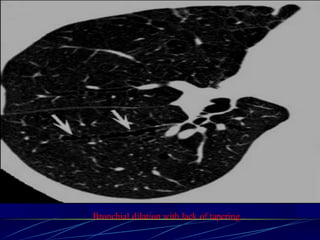

Paraseptal (distal acinar)

emphysema

Affects the peripheral parts of

the secondary pulmonary lobule

Produces subpleural lucencies.

Paraseptal emphysema